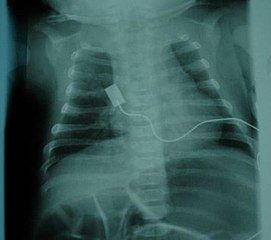

| 제1형 | 베르드니히-호프만병 (Werdnig-Hoffmann disease) | 출생 후 6개월 미만 | 가장 흔하고 심각한 유형 (약 50%). 전신적인 심한 근력 저하 및 근육긴장저하(플로피 인펀트). 임신 중 태동 약화 가능성. 도움 없이 앉기 불가능, 머리 가누기 불가능. 안면근 약화, 빨기/삼키기 어려움, 흡인, 호흡 부전 동반. 늑간근 약화로 인한 기이 호흡(흡기 시 흉부 함몰). 혀의 섬유속성 연축, 심부건 반사 소실. 인공 호흡기 없이는 평균 6~9개월 생존, 대부분 2년 이내 사망. |

| SMA 1 (영아형) | 베르드니히-호프만병 | 0~6개월 | 가장 흔한 형태로 환자의 약 50%를 차지한다. 생후 몇 주 또는 몇 달 내에 질병이 나타나며, 빠르게 진행되어 다양한 근육 그룹의 기능 장애를 일으킨다. 영아는 도움 없이 앉는 법을 배우지 못하고 점진적으로 근육 기능을 상실한다. 주요 사망 원인은 호흡 근육 기능 부전으로 인한 폐렴(특히 흡인성 폐렴)이다. 조기 호흡 지원 및 약물 치료 없이는 대부분 생후 2년을 넘기지 못한다. 그러나 적절한 호흡 지원을 받으면 증상이 덜 심한 일부 환자(SMA 1형의 약 10%)는 약물 치료 없이도 청소년기 및 성인기까지 생존하는 경우가 있으며, 이 경우 지속적인 간호가 필요하다. 특징적인 증상으로는 심한 전신 근긴장저하 (플로피 인펀트), 머리 제어 불가능, 안면근육 약화, 수유 및 연하 곤란, 혀 근육의 떨림(섬유 다발 연축), 기이 호흡 등이 있다. 심부건 반사는 소실된다. | 253300 |

호흡계는 척수성 근위축증(SMA)에서 가장 흔하게 영향을 받는 계통이며, 특히 SMA 0/1형 및 2형에서 호흡기 합병증은 주요 사망 원인이다. SMA 3형도 드물지만 유사한 호흡기 문제를 겪을 수 있다.[58] 이러한 합병증은 신경 자극 부족으로 인해 늑간근이 약해져서 발생하며, 횡격막은 상대적으로 덜 영향을 받는다.[58] 약해진 근육은 호흡과 기침 능력을 완전히 회복하기 어렵다. 이로 인해 호흡이 힘들어지고, 충분한 산소를 얻지 못하거나 얕은 호흡을 하게 되며, 기도 분비물을 효과적으로 제거하지 못할 위험이 있다. 이러한 문제는 근육이 더 이완되는 수면 중에 더 흔하게 나타난다. 또한, 인두의 삼킴 근육(연하 근육)이 약해지면 음식물이나 분비물이 기도로 넘어가는 흡인이 발생할 수 있으며, 약한 기침 능력과 결합되어 폐렴과 같은 감염 위험을 높인다.[59]호흡 관리를 위해서는 다음과 같은 방법들이 사용된다.

- 호흡 보조: 폐 근육 약화로 인한 호흡 곤란을 돕기 위해 비침습적 인공호흡(BiPAP)이 자주 사용된다. 이는 일종의 양압기로, 마스크 등을 통해 공기를 불어넣어 호흡을 보조한다. 상태가 더 심각한 경우에는 기관 절개술을 시행하여 직접 기도에 관을 삽입해 호흡을 보조하기도 한다.[60] BiPAP과 기관 절개술 모두 생존 기간을 비슷한 정도로 연장하는 효과가 있지만, 기관 절개술은 언어 발달에 어려움을 줄 수 있다.[61]